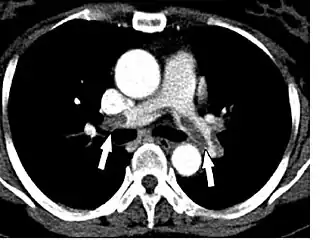

- Le scanner spiralé des artères pulmonaires[13] ou angioscanner des artères pulmonaires : un produit de contraste iodé est injecté en intraveineux. Le mouvement rotatif et longitudinal (caractère spiralé) de la tête du scanner permet de bien visualiser les artères pulmonaires proximales et moyennes et un peu moins bien leur distalité. C’est un excellent examen de diagnostic positif et de gravité, même si les risques liés à l’emploi de produits iodés et la radiation persistent. Il est moins invasif que l'angiographie conventionnelle. Il permet aussi l'évaluation de plusieurs autres structures intrathoraciques (aorte et médiastin, poumon, plèvre), en plus de l'évaluation des artères pulmonaires. Il est considéré souvent comme le nouvel examen de référence.